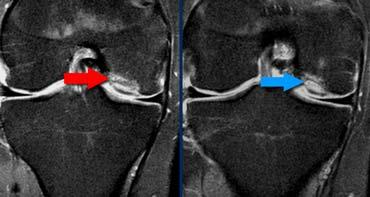

Lưu ý rằng trên ảnh mặt phẳng vành và mặt phẳng ngang, các bó sợi ACL nằm sát ngay bên cạnh xương của hõm liên lồi cầu (mũi tên).

Tuyệt đối không được có dịch giữa các bó sợi ACL và xương lồi cầu ngoài (gọi là ‘dấu hiệu hõm rỗng’).

TRÁI: Các bó sợi ACL có hướng bình thường nhưng không bám vào lồi cầu đùi. PHẢI: Dấu hiệu hõm rỗng: dịch áp sát mặt trong lồi cầu ngoài.

Đôi khi dễ đánh giá hơn liệu các bó sợi có còn bám vào xương hay không khi quan sát trên mặt phẳng vành.

Tuyệt đối không được có dịch áp sát mặt trong lồi cầu ngoài.

Nếu có dịch ở vị trí này, được gọi là ‘dấu hiệu hõm rỗng’, cho thấy ACL đã bị bong khỏi điểm bám trên lồi cầu đùi.